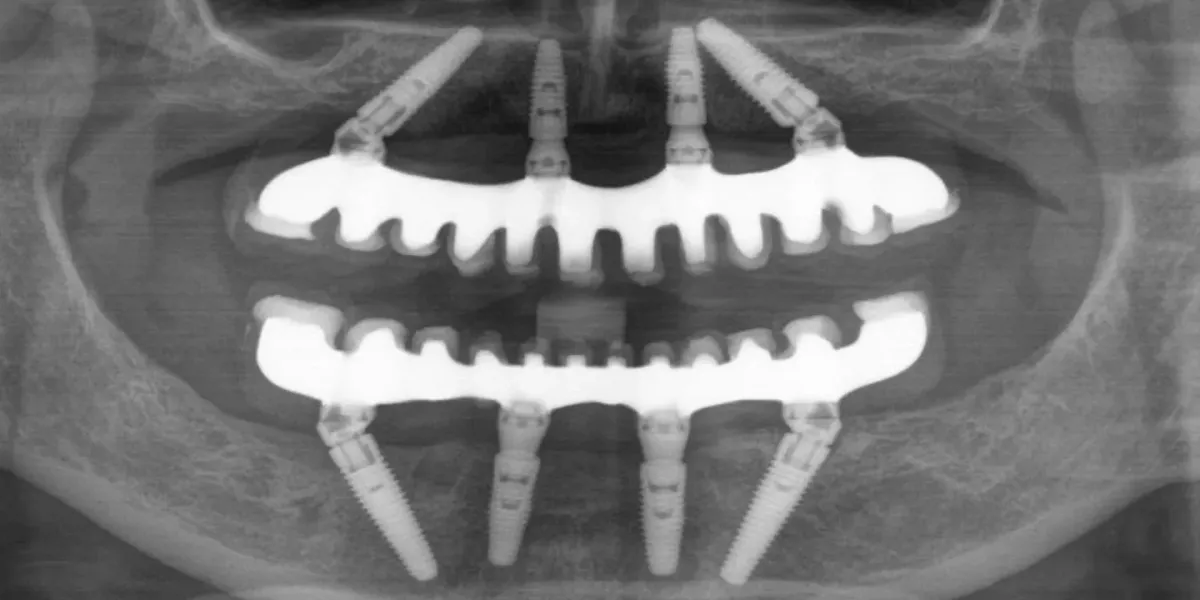

Terapija se temelji na ugradnji četiri implantata u čeljust koji služe kao stabilna sidrišta za fiksni zubni most.

Zahvaljujući pažljivom planiranju terapije i preciznom rasporedu implantata moguće je nadomjestiti cijeli zubni niz, često bez dodatnih kirurških zahvata poput regeneracije kosti.

Terapija započinje konzultacijama, pregledom i suvremenom dijagnostikom, uključujući 3D rendgensko snimanje. Na temelju pregleda izrađuje se individualni plan terapije i određuje optimalno rješenje.

Ugradnja implantata

Tijekom kirurškog zahvata ugrađuju se četiri implantata koji služe kao stabilna sidrišta za zubni most. Zahvat se planira precizno kako bi se osigurala stabilnost i dugoročna funkcija.